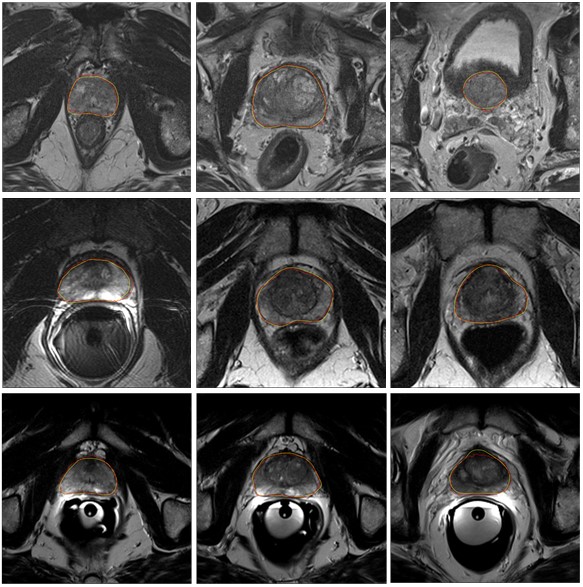

图一:前列腺分割面临的挑战:(a)前列腺区域存在大量的噪声;(b)前列腺边缘模糊;(c)前列腺周边的组织与前列腺的分布特征类似。

图二:部分分割结果。黄色轮廓线为专家标记结果,红色轮廓线为我们所提方法分割结果。